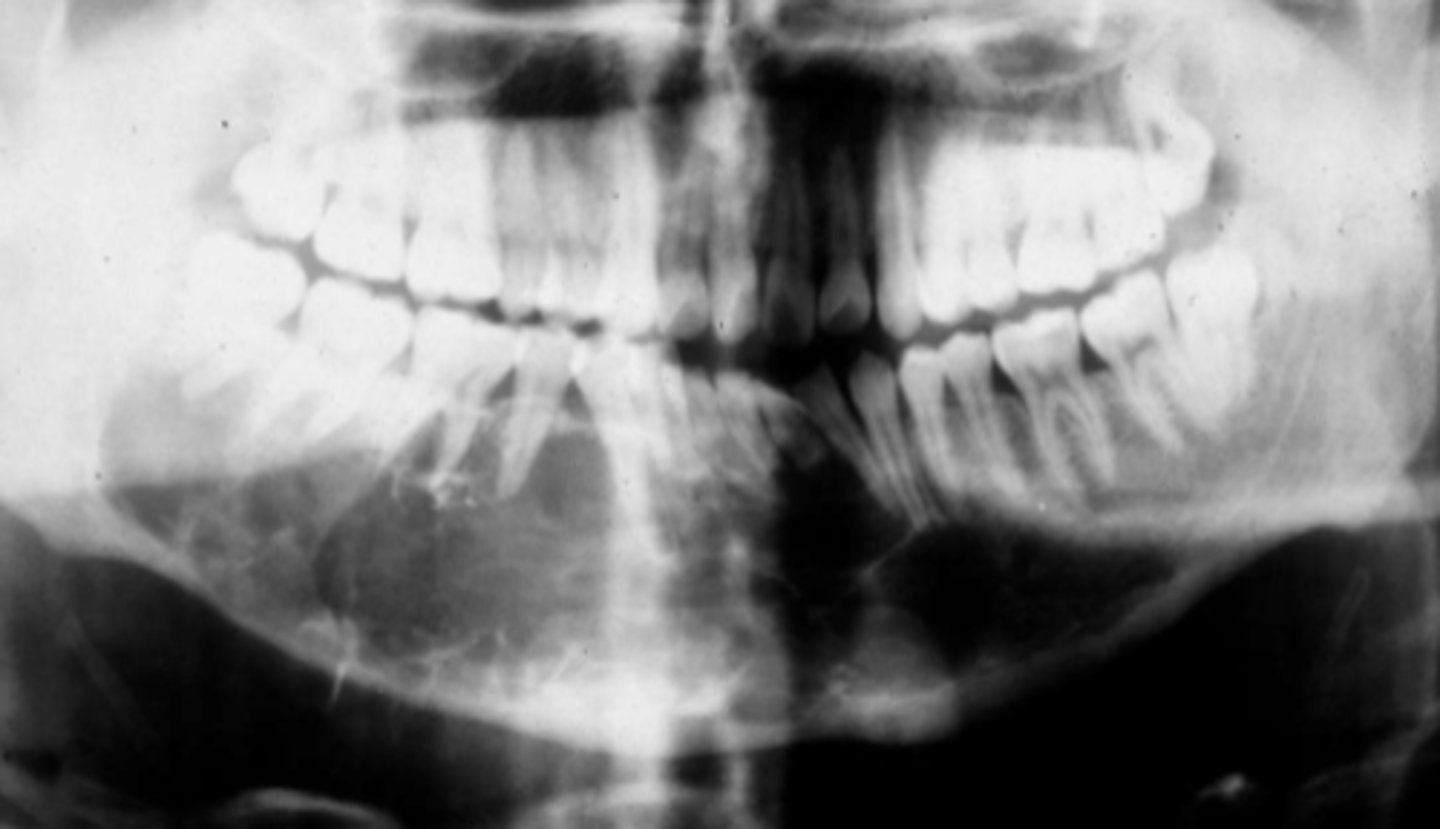

how would you describe this lesion?

A. well-defined, periapical radiolucent lesion associated with #24 and 25

B. ill-defined, periapical radiolucent lesion associated with #24 and 25

C. well- defined, multilocular periapical lesion associated with tooth number 24 and 25

D. mixed density, periapical lesion associated with teeth number 24 and 25

- Also note loss of apical lamina dura of 24, 25

What category would this lesion be part of?

Dysplasia

What would be a differential diagnosis for this lesion?

PCOD (stage 1)

How would you describe the following lesion?

Multiple mixed density periapical target-like entities

The teeth are vital. What category would you put this lesion into?

dysplasia (PCOD)

what could be a differential diagnosis for this lesion?

A. radicular cyst

B. periapical granuloma

C. PCOD (stages 2/3)

D. apical rarefying osteitis